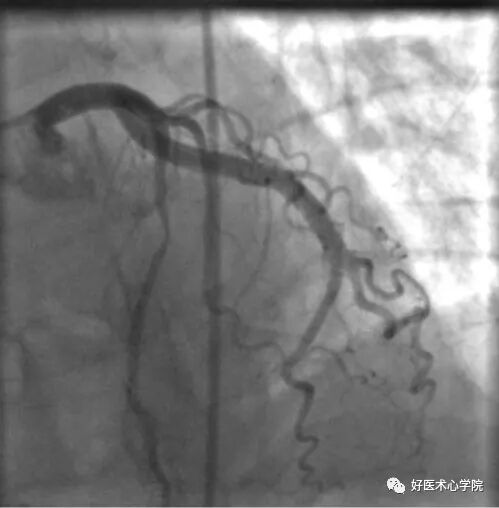

左前斜位:观察右冠全长,但难以看到远段分叉。

此时可以加足位可以观察。

△左前斜位下的右冠